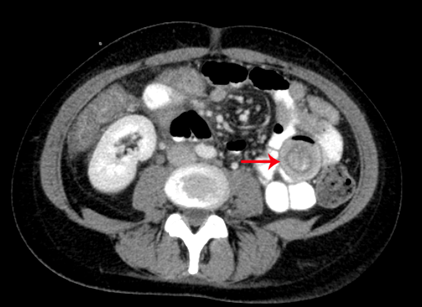

Abb.4: Neutropene Enterokolitis im Jejunum. Typisches Bild eines Target Zeichens (Pfeil). Kontrastmittelaufnahme der Mukosa und ödematöse Wandverdickung.